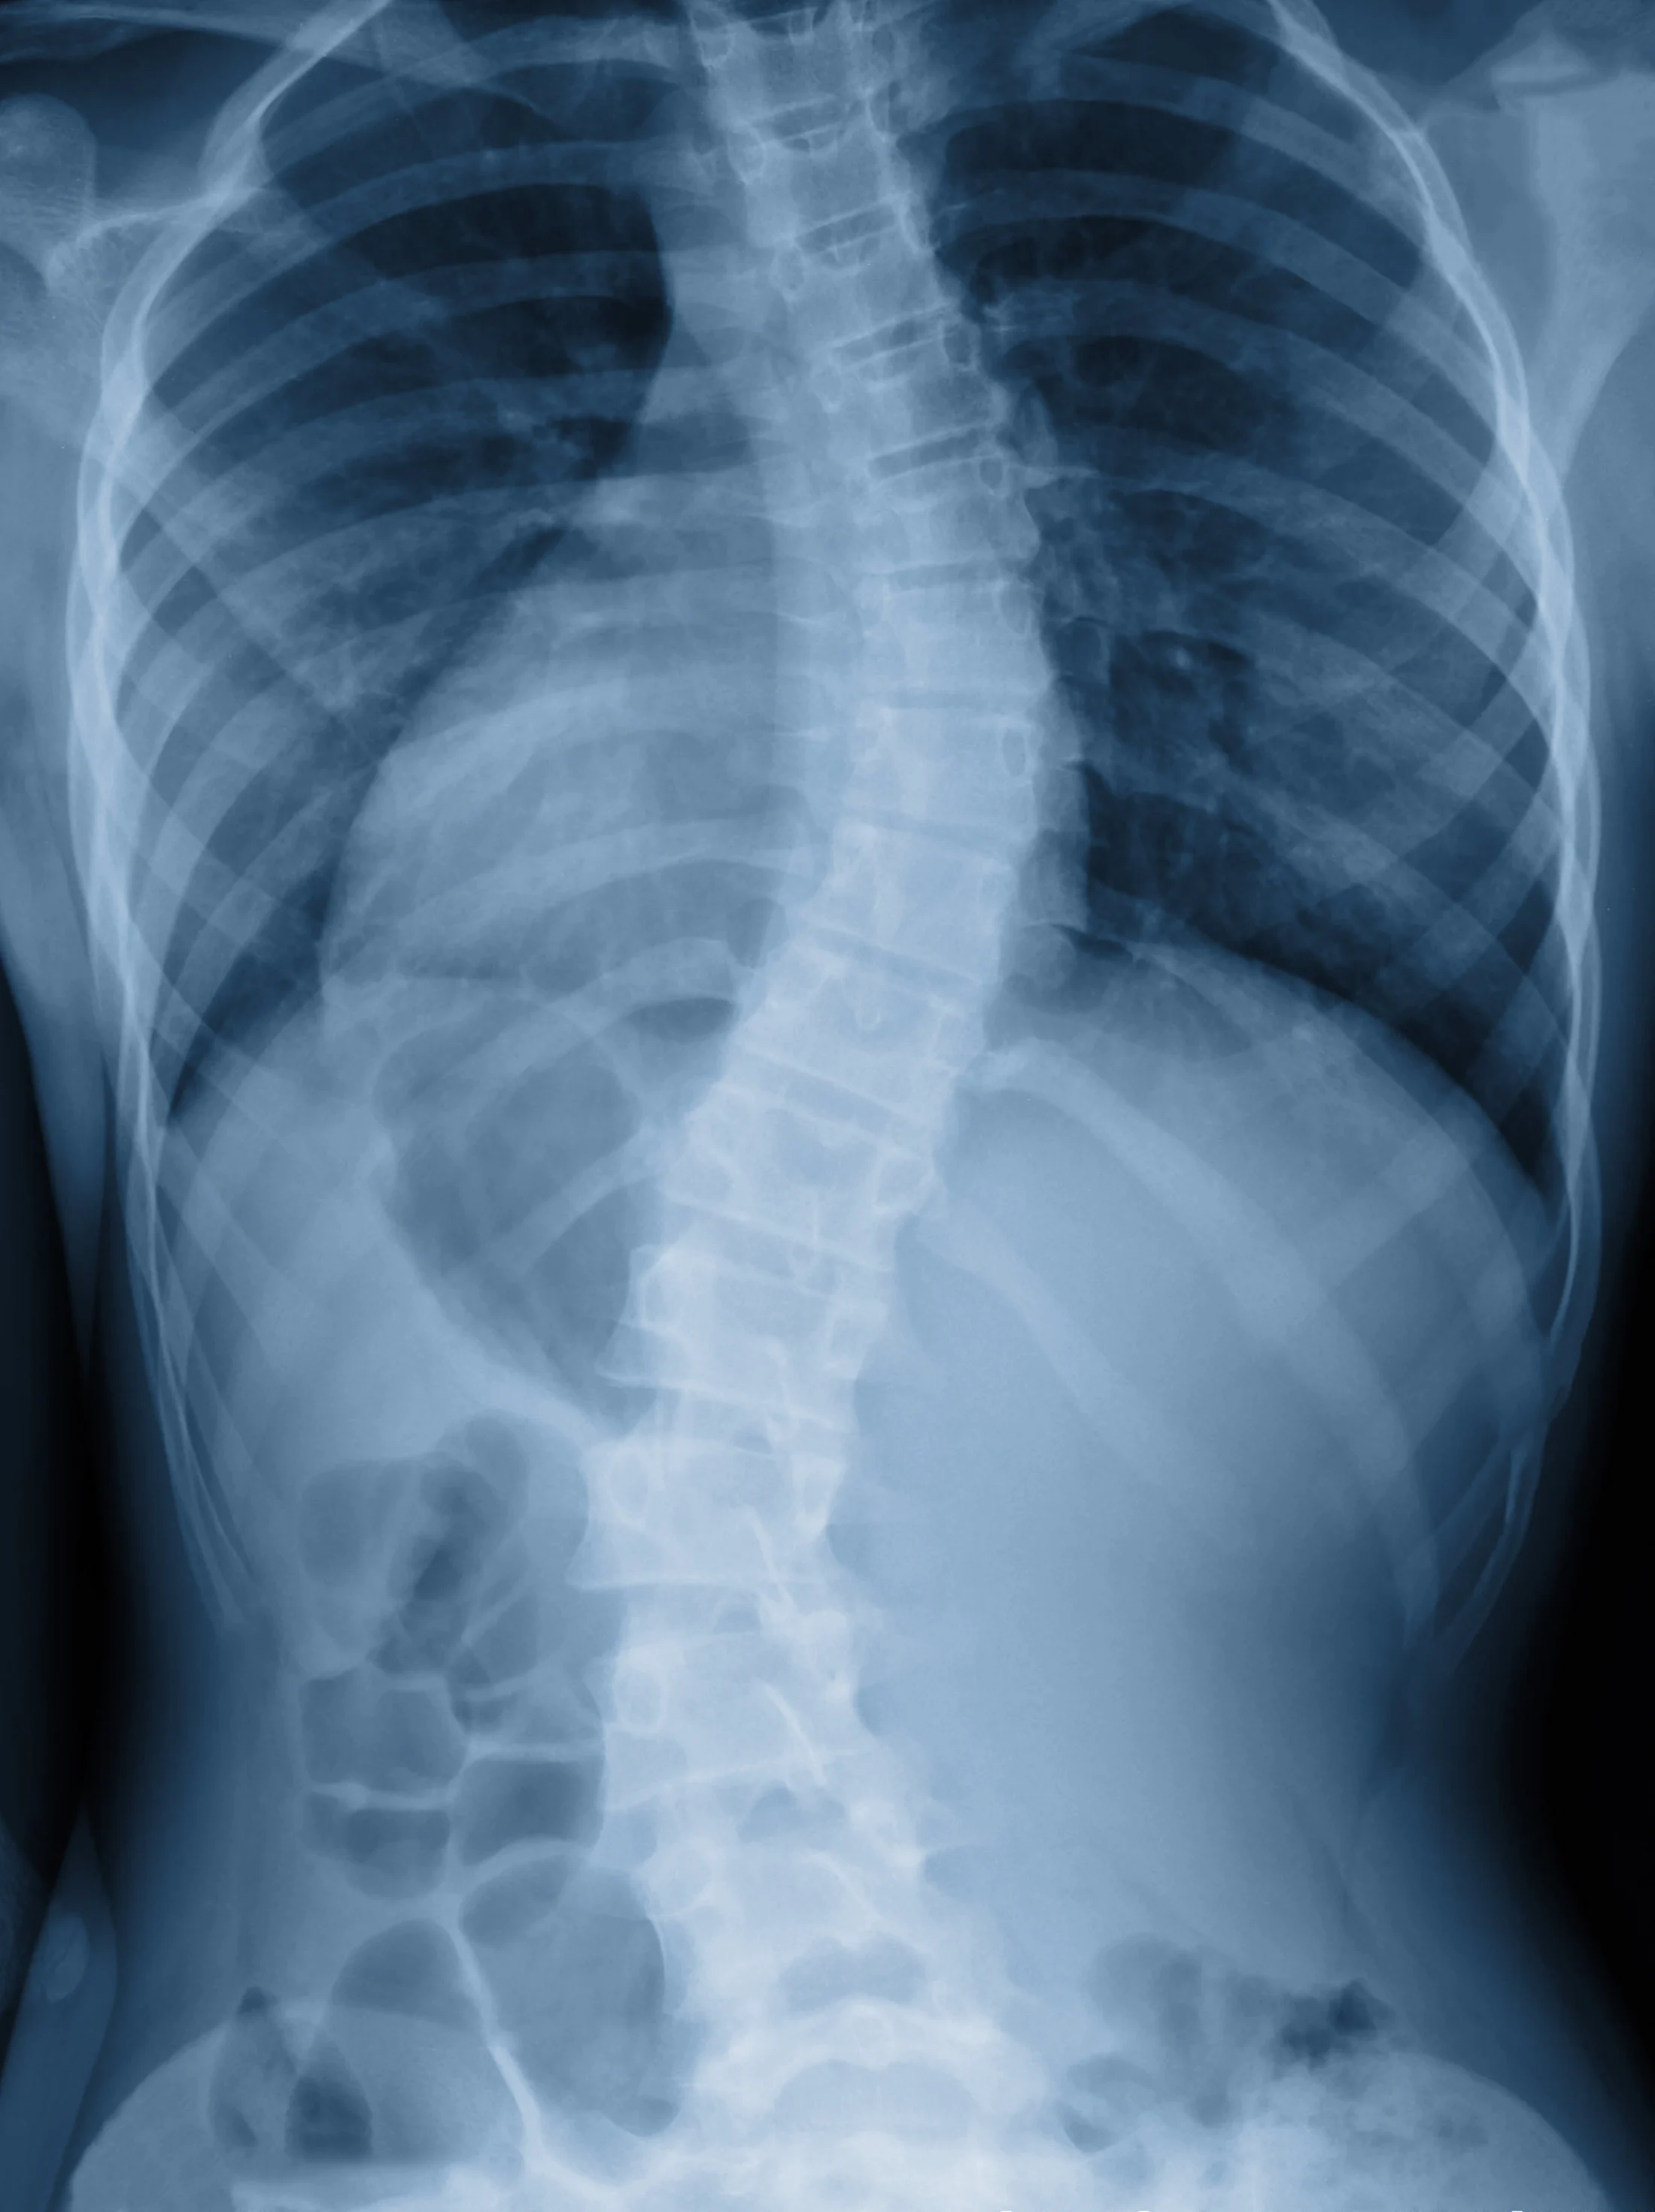

Noticing a lateral curvature in an adolescent's back is an early indicator of scoliosis.

- Sideways curvature observed while in bathing suit or changing. For instance, a parent could first notice the sideways curvature in an adolescent’s back while at the pool or beach.